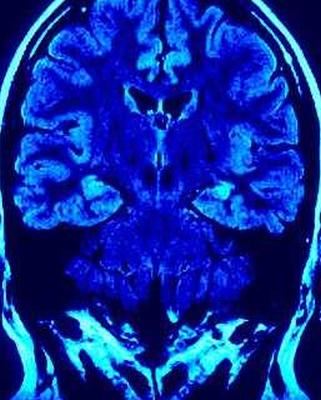

Другие, менее распространенные симптомы могут включать депрессию, трудности с глотанием или жеванием, прерывистый сон, кожные заболевания и трудности с функциями организма. Болезнь Паркинсона трудно диагностировать, так как в настоящее время не существует окончательного анализа крови или сканирования мозга, которые точно идентифицировали бы болезнь Паркинсона, исключая при этом другие расстройства. Диагноз обычно основывается на неврологической оценке и истории болезни.